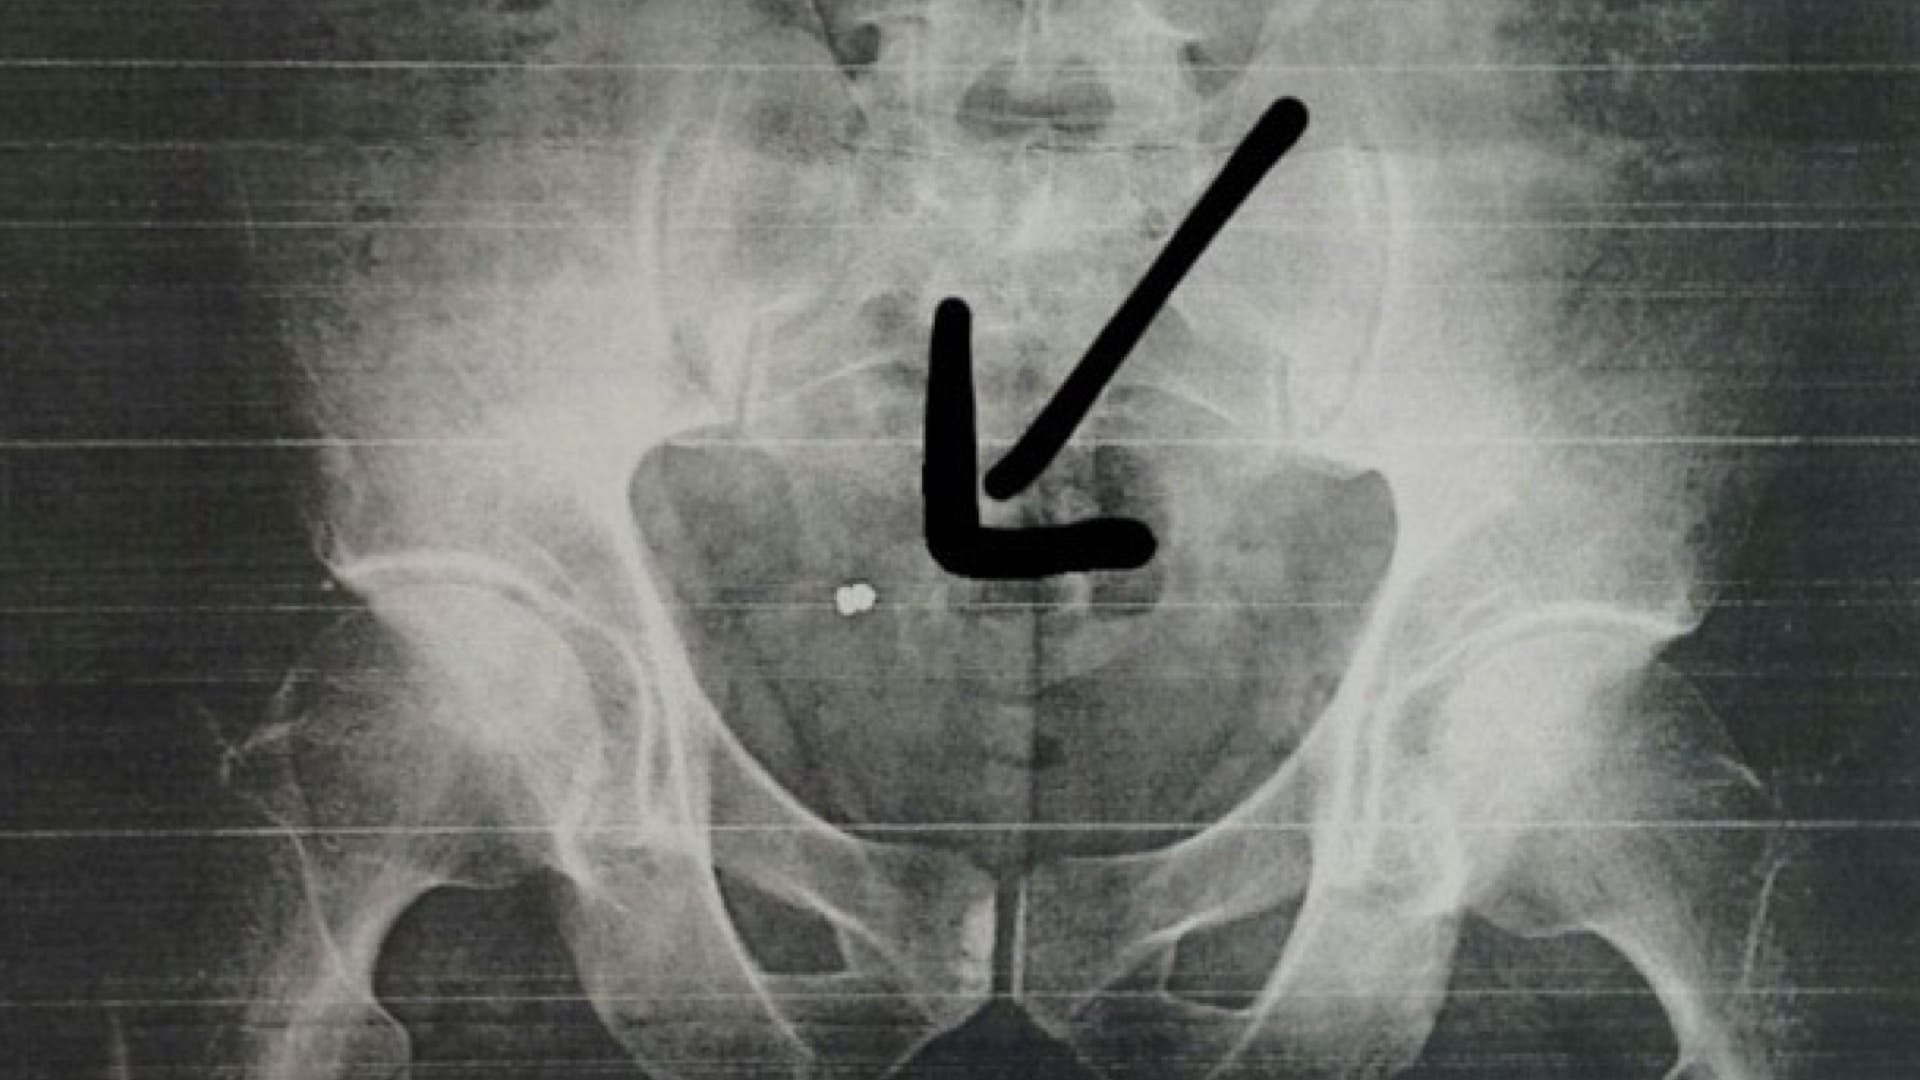

Fue en su casa cuando se dio cuenta de que tenía un orificio, volviendo al día siguiente a la mutua donde ya sí le hicieron una radiografía y comprobaron que tenía un perdigón incrustado en su nalga derecha, como se puede ver en la imagen que publicamos a continuación, cedida por El Heraldo del Henares.

El empleado municipal fue derivado al Hospital de Fremap en Majadahonda donde, una semana después, será operado este jueves para poder extraerle el perdigón.